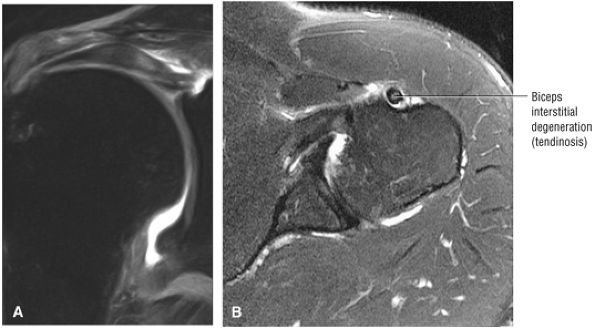

the bicipital groove. The sagittal plane is useful in identification of tendinosis of the proximal biceps tendon both within the rotator interval and at the proximal bicipital groove. Complete tears with retraction of the biceps tendon into the bicipital groove are displayed as absence of the biceps tendon within the rotator interval.